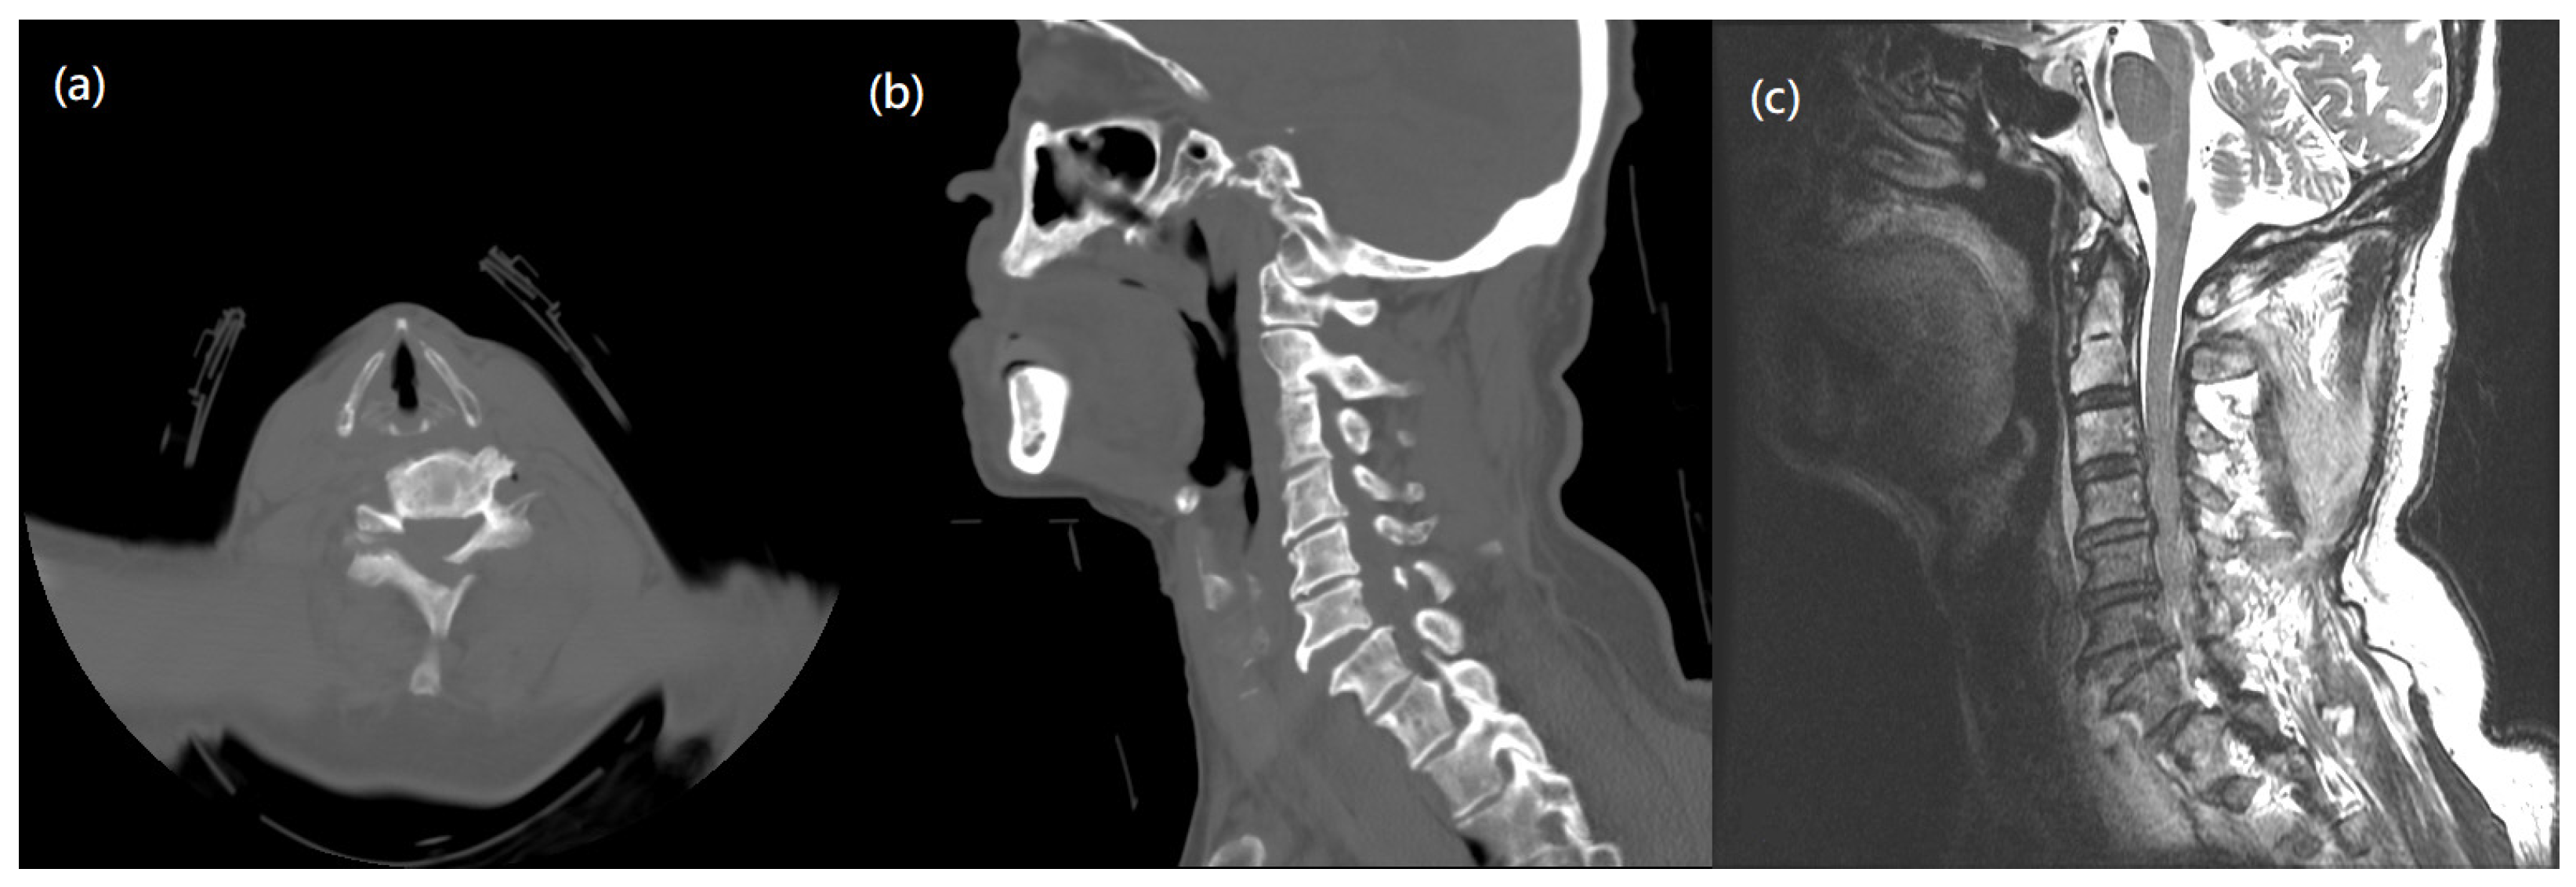

The patient, an 87-year-old man, presented at our rehabilitation ward with postoperative weakness over both lower limbs. He had a traffic accident, leading to an incomplete type of cervical spinal cord injury. On the American Spinal Injury Association (ASIA) impairment scale, the injury was categorized as grade D. Initially, he had neck pain, bilateral upper limb numbness over bilateral C5-C7 dermatome, and weakness over all four limbs, with a muscle strength grade of 3/5. Preoperative computed tomography (CT) and magnetic resonance imaging (MRI) revealed a fracture in posterior element of C5-C6, and anterior subluxation of C6-C7 with disc posterior herniation compressing the spinal cord (Figure 1). We performed emergent decompression of C6 and C7, and anterior cervical discectomy and fusion (ACDF) of C6-C7 with cervical spine locking plates (CSLP) for fixation. After the operation, he had partial relief of neck pain, numbness, and limb weakness. Rehabilitation programs were then arranged. One week later, his muscle strength over four limbs gradually improved to grade 4/5, and he was able to tolerate a standing position with fair balance. As for his medication history, besides NSAIDs for pain management after surgery, he was also taking metformin, basal insulin for type 2 diabetes mellitus, an alpha blocker for benign prostate hypertrophy, and a proton pump inhibitor for a gastric ulcer. He was a social drinker and had family history of hypertension and diabetes mellitus.

Figure 1. Pre-operative images. (a) Axial view of C spine CT showed a fracture in posterior element of C5-C6. (b) Sagittal view of C spine CT demonstrated traumatic spondylolisthesis of C6 on C7. (c) MRI T2-weighted image of C spine showed anterior subluxation of C6-7 with posterior HIVD, compressing the spinal cord, and soft tissue swelling in dorsal neck.